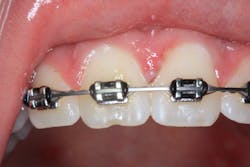

Clinical assessment revealed multiple white lesions with red borders salt-and-peppered in a generalized fashion throughout the entire oral cavity. The gum tissues were swollen and any light palpation/touching of the lesions resulted in bleeding and pain. See clinical photos below.